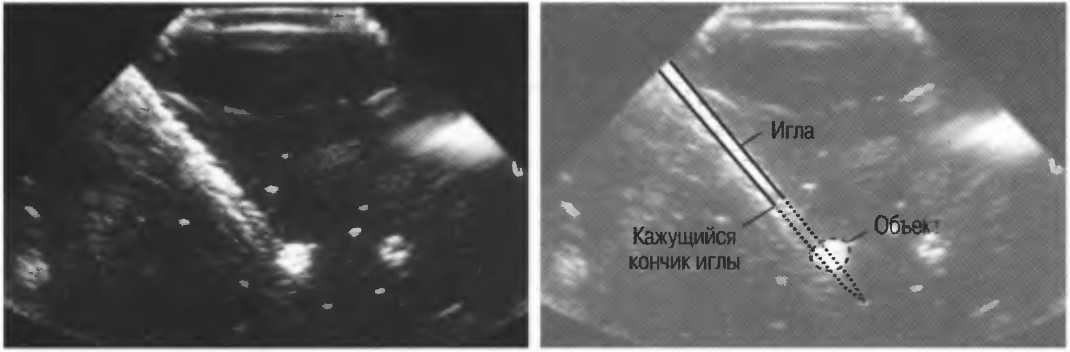

На практике, наиболее значимые в клиническом плане артефакты возникают при проведении биопсии или аспирации под контролем ультразвука. До тех пор пока кончик иглы не появится в плоскости сканирования на экране, он не будет визуализироваться, и может создаться ложное представление о том, что игла значительно короче (рис. 21в).

Рис.21 в. Изображение иглы в емкости с водой. Слева игла находится в плоскости сканирования не полностью, в результате чего выглядит короче, чем есть на самом деле (крестик определяет реальную глубину проникновения иглы). Справа игла визуализируется полностью.